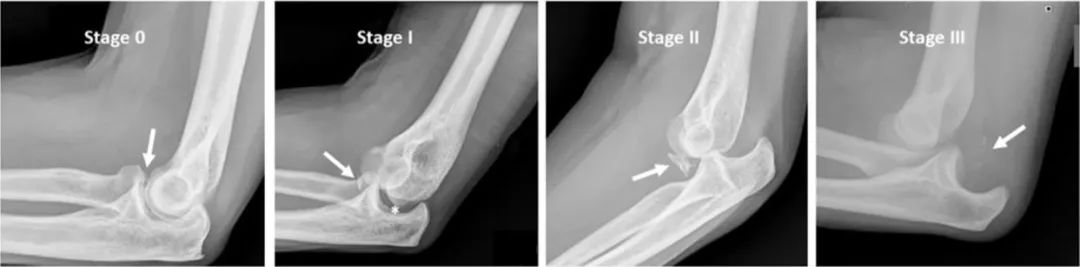

图3 多个肘侧位 X 光片显示肘关节脱位中描述的不同阶段。0期:正常对齐。注意冠状突骨折(箭头)。I 期:后外侧旋转不稳 (PLRI),伴有轻度不协调和尺侧滑车关节间隙扩大 > 4 mm(下降征)。另外,注意桡骨头相对于小头的后移。箭头:冠状突骨折。II 期:尺肱关节脱位伴冠状突骨折(箭头)。III 期:尺肱关节完全脱位伴小骨折块(箭头)